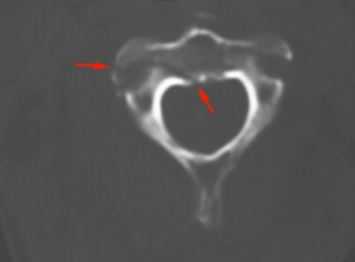

КТ является методом выбора для оценки костного повреждения. Однако более полную информацию о состоянии спинного мозга даёт МРТ.

КТ. Перелом тела С2 (красные стрелки).